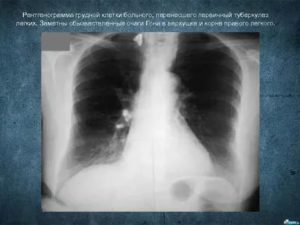

В повседневной жизни человек неоднократно сталкивается с возбудителем туберкулеза легких, даже не замечая этого. Подтверждением этому являются «случайные» находки при прохождении ежегодной плановой флюорографии, которые представляют собой очаги Гона. Как они формируются и несут ли опасность для организма, рассмотрим в этой статье.

Очаг Гона в легких является результатом первичного инфицирования человека микобактерией туберкулеза. Длительность его формирования в среднем составляет до 3 лет. Очаг Гона представляет собой овальное образование, иногда с неровными лучистыми контурами. Структура его представлена соединительной тканью, коллагеновыми волокнами, отложениями кальция. Размеры могут достигать 2 см.

При рентгенологических исследованиях очаг Гона представляет собой затемнение овальной (реже округлой) формы с резкими очертаниями, размерами до 5 мм. Образования могут быть единичными и множественными. Излюбленная их локализация – нижние и средние отделы легких. Иногда контуры очага могут быть неровные. Легочный рисунок неизменен, корень не расширен.

На разных этапах петрификации (обызвествления) очага Гона изменяется, структура его может быть:

- гомогенной (однородной),

- негомогенной: имеет зернистое или дольчатое строение, неровные границы.